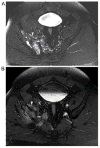

Purpose: To evaluate the frequency of tumor thrombus in the large veins draining primary pelvic osteosarcoma on early cross-sectional imaging studies and its effect on patient survival.

Materials and methods: Our retrospective study included all patients with primary pelvic osteosarcoma treated at our facility between January 2000 and May 2014, who were ≤ 45 years of age, and had adequate imaging studies and clinical follow up. Four radiologists evaluated for tumor in the large draining veins on initial CT, MRI and PET/CTs. A consensus evaluation by the four radiologists together with findings on operative reports, pathology reports or follow-up imaging was used as the reference standard.

Results: Thirty-nine patients with primary pelvic osteosarcoma met final inclusion criteria. Tumor thrombus was identified in the large draining veins in 10 of the 22 (45%) patients who underwent tumor resection and 10 of the 17 (59%) who did not. In the 22 patients who underwent tumor resection, tumor thrombus was significantly associated with worse overall survival (p = 0.03).

Conclusions: Tumor thrombus in the large draining veins is identified in a significant proportion of initial imaging studies in patients with pelvic osteosarcoma, and is associated with worse overall survival in patients who undergo tumor resection.